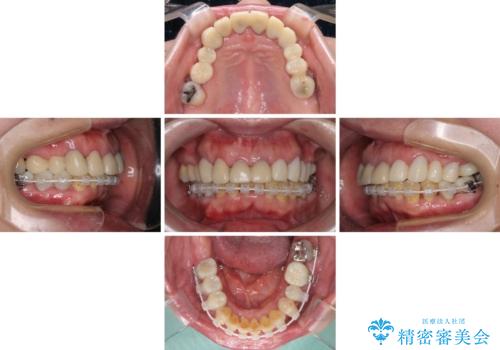

まずは抜歯が必要な歯を抜歯した上で仮歯に置き換え、インプラント埋入や歯周外科処置、根管治療を行うこととしました。

歯肉の状態が落ち着いた後に下顎の矯正治療を行い、その後補綴治療を行うこととしました。

インプラントに対する恐怖心が強く、欠損補綴は極力ブリッジを採用し、インプラントの数は必要最小限としました。